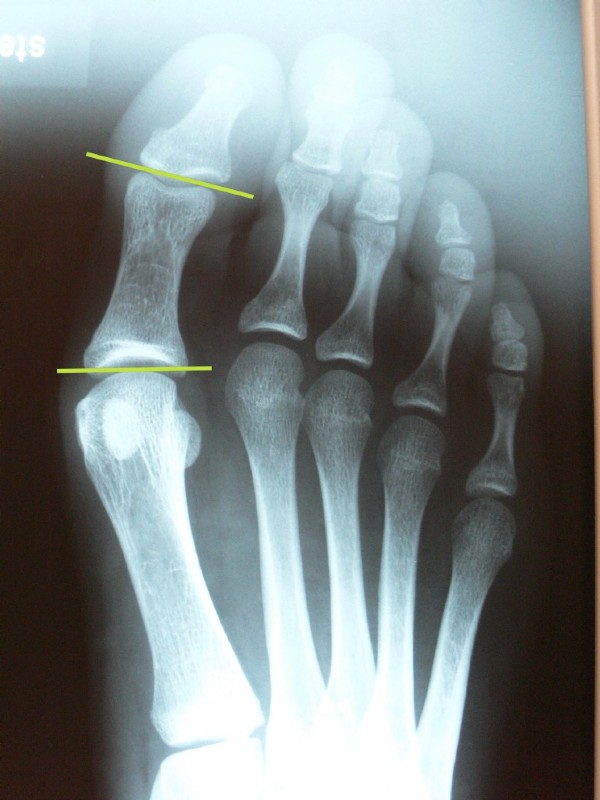

Nach der Korrektur stehen die Zehengelenke parallel (horizontale grüne Striche), das "Überbein" ist weg, der 1. Mittelfußknochen ist dem 2. angenähert und der Fuß wird schmäler.

Am 1. Mittelfußknochen ist unsere "Interferenzschraube" zu sehen, die die versetzte Adduktorsehne befestigt.